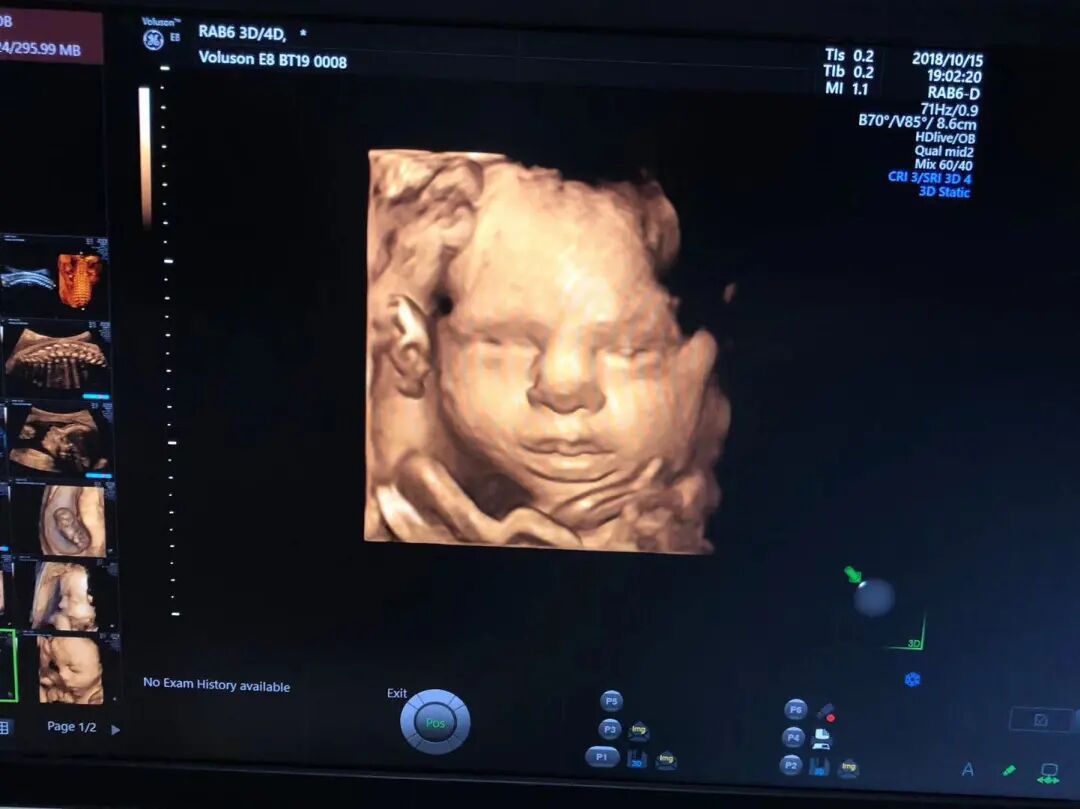

开展四维彩超检查——拥有世界先进的超声设备,包括实时四维彩超诊断仪2台(美国GE-E8和西门子OXANA 2),2018年1月起聘请厦门三甲医院超声专家定期坐诊,为广大孕妇提供优质的胎儿检查服务。

美国GE—煊光E8四维彩超高清效果图